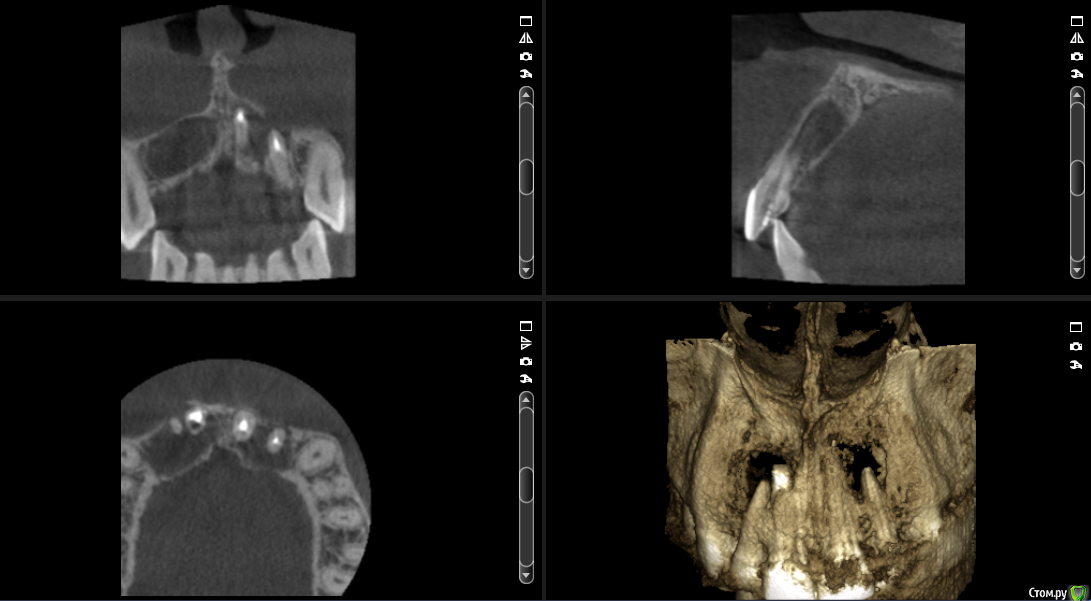

___49___ Опубликовано 5 декабря, 2016 Поделиться Опубликовано 5 декабря, 2016 Что скажите коллеги - интересно ваше мнение , советы. 11 зуб - канал разбит - пока не решил, что с ним делать. Остальные зубы однозначно хочу оставить + эндо 12 му. А после резекция..... Ссылка на комментарий

___49___ Опубликовано 5 декабря, 2016 Автор Поделиться Опубликовано 5 декабря, 2016 Пробуйте ортоградно. МТА в помощь...Опешите пожалуйста подробней как вы бы это выполнили ? я думаю - канал ортоградно перелечить в 11 , эндо в 12 и после резекцию с ретроградкой МТА. Ссылка на комментарий

Евгений Ходыкин Опубликовано 6 декабря, 2016 Поделиться Опубликовано 6 декабря, 2016 Опешите пожалуйста подробней как вы бы это выполнили ? я думаю - канал ортоградно перелечить в 11 , эндо в 12 и после резекцию с ретроградкой МТА.При таких "разбитых" апексах всё отмываете, апексифицируете МТА. Выше можно и гутту. Ничего по не резецировать. Сделайте КТ через год, там и оцениваете результат... Ссылка на комментарий